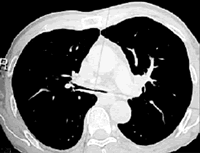

辅助检查 肝肾功能无异常,免疫系统各项指标(-),血总IgE水平正常,心电图(-)。血气分析正常。纤维支气管镜检查示:主气管及各级支气管黏膜充血、水肿,可见大量分泌物,主气管下段、双侧主气管及双侧各级支气管可见呼气相明显狭窄,左肺上叶及右中叶支气管开口狭窄(图1)。

纤维支气管镜检查提示气管及支气管呼气相塌陷,诊断不除外复发性多软骨炎(RP),再查体发现鼻梁塌陷。询问病史,鼻梁塌陷在近1年内明显。复阅胸部 CT发现,呼吸相,主气管较正常人气管明显缩窄,左右支气管分叉显示内径明显狭窄(图2)。